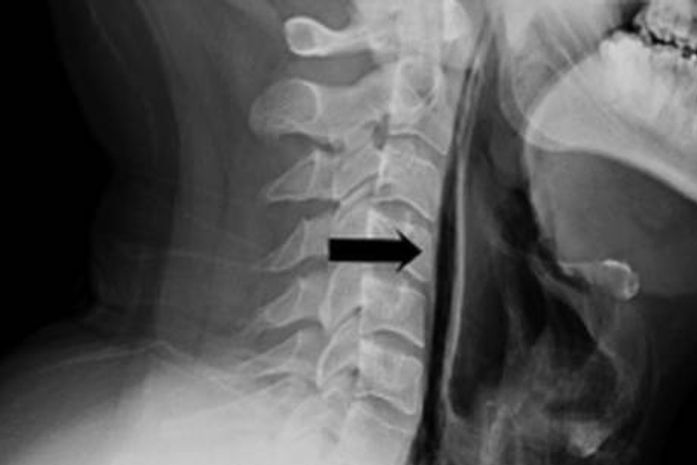

Como o espirro não tinha para onde escapar, a pressão rasgou o tecido mole da garganta. Um

raio-X revelou que havia ar escapando da traqueia do paciente. Ele ficou internado por uma semana, recebendo alimentação via tubo, até se recuperar.